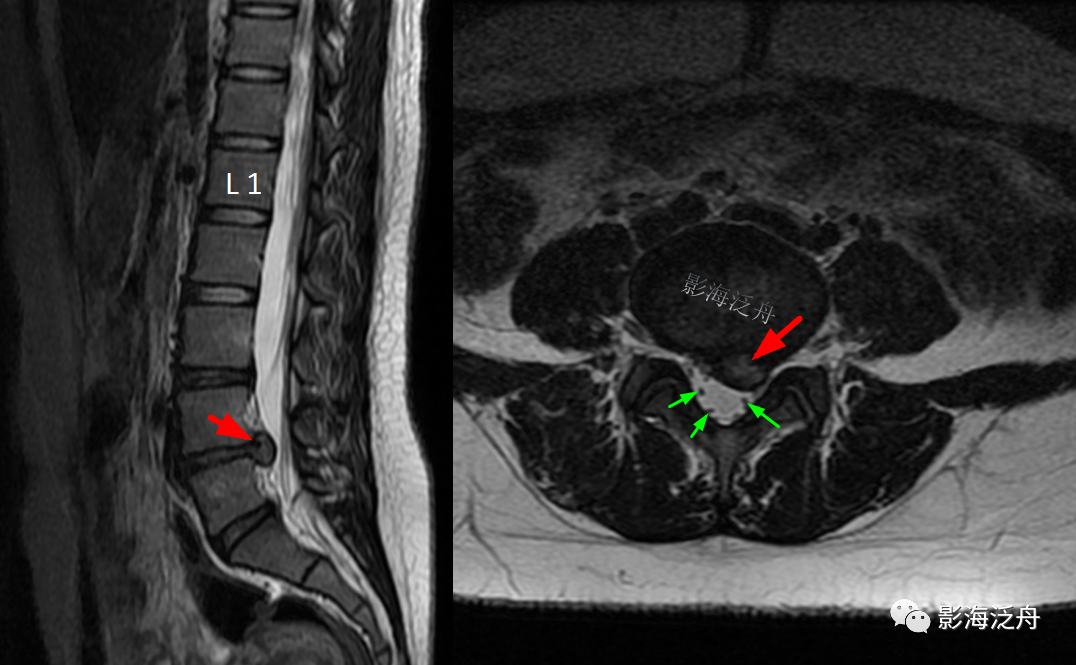

正常的腰骶部MR解剖:在脊髓圆锥(红箭)水平以下,椎管内走行的主要是终丝及马尾神经(黄箭),大量脑脊液填充在硬膜囊内(蓝箭头);硬膜囊以外的椎管内只有少量脂肪组织填充(绿箭头)。

病例一:患者男,27岁,搬重物后腰疼半天。可见L4/5椎间盘明显向左后方突出(红箭),硬膜囊受压明显,但硬膜囊内的马尾神经分布基本正常(绿箭)。